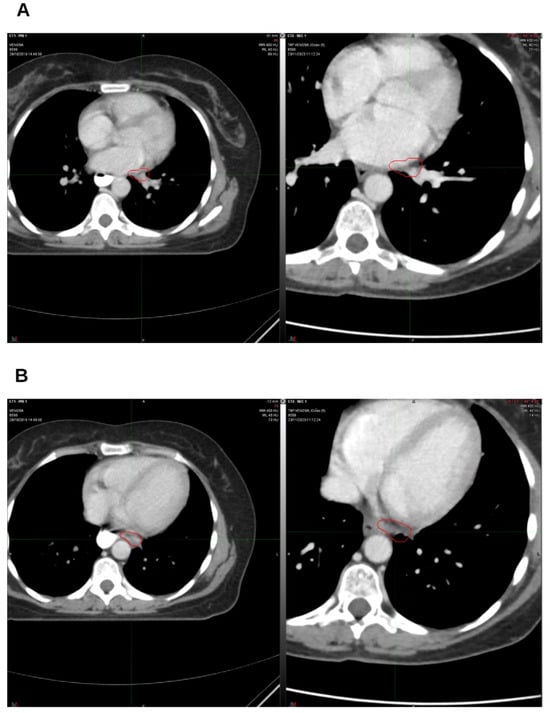

Integrative Use of Cannabidiol, Melatonin, and Oxygen–Ozone Therapy in Triple-Negative Breast Cancer with Lung and Mediastinal Metastases. A Case Report

Background and Clinical Significance: Breast cancer is the most frequent malignancy in women. Metastatic breast cancer is considered a treatable but incurable condition, with a median overall survival of only 2–3 years. Among its subtypes, triple-negative breast cancer (TNBC) accounts for a high proportion of breast cancer-related deaths. It is characterized by an aggressive clinical course, early recurrence, and a strong propensity for visceral and brain metastases. Case Presentation: We report the case of a Caucasian woman who developed systemic disease recurrence with lung and mediastinal lymph node metastases, occurring two years after her primary diagnosis and treatment for TNBC. The patient received three months of chemotherapy combined with an adjuvant integrative protocol consisting of melatonin, cannabidiol, and oxygen–ozone therapy. This combined approach led to the complete disappearance of the lung nodules. Subsequently, stereotactic radiotherapy was performed and, in association with the ongoing integrative treatment, resulted in a significant reduction in mediastinal adenopathy. Introduction of immunotherapy, supported continuously by the same adjuvant strategy, achieved a complete and durable remission. Strikingly, the patient remained disease-free five years after the diagnosis of lung and mediastinal metastases. Conclusions: This clinical case highlights the potential benefit of using melatonin, cannabidiol, and oxygen–ozone therapy as part of an integrative approach in patients with aggressive metastatic TNBC. While it is not possible to establish causality from a single case, the sustained remission observed suggests that such unconventional adjuvant strategies could play a supportive role in enhancing the efficacy of standard oncologic therapies. Full article

Show Figures

Figure 1